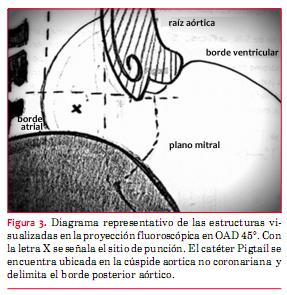

Si bien el dispositivo de cierre se implanta por vía transvenosa, la técnica de punción transeptal utilizada requiere de un acceso arterial adicional. Los accesos utilizados en los dos casos fueron uno venoso por punción venosa femoral derecha (7 Fr) y uno arterial por punción de la arteria radial izquierda (6 Fr). Para guiar la punción transeptal se introdujo un catéter Pigtail por el acceso arterial, que se ubicó en el seno de Valsalva no coronariano. Esto permitió delinear el borde posterior de la raíz aórtica, evitando dicho sector durante la punción. Esta se realizó con aguja de Brockenbrough guiada por radioscopía y por ETE.

La fosa ovalis es la zona donde se debe realizar la punción. En la proyección OAD 45°, la misma se debe ubicar por debajo del plano horizontal de la válvula aórtica (1-3 cm) a mitad de distancia entre el borde posterior aórtico y el borde posterior de la silueta auricular(7,8) (figura 3).